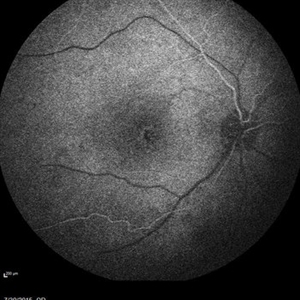

Retinal Dystrophy of 24-Year-Old Male/ Red Free OD

Nov 25 2015 by Zach Dupureur

Fluorescein angiography of a 24-year-old male. Juvenile retinoschisis on OCT. FA shows outer retinal staining. Could be associated with Goldman Farve Syndrome.

Photographer: Zach Dupureur OCT-C

Imaging device: Heidelberg Spectralis

Condition/keywords: Goldmann-Favre Syndrome, juvenile retinoschisis, retinal dystrophy